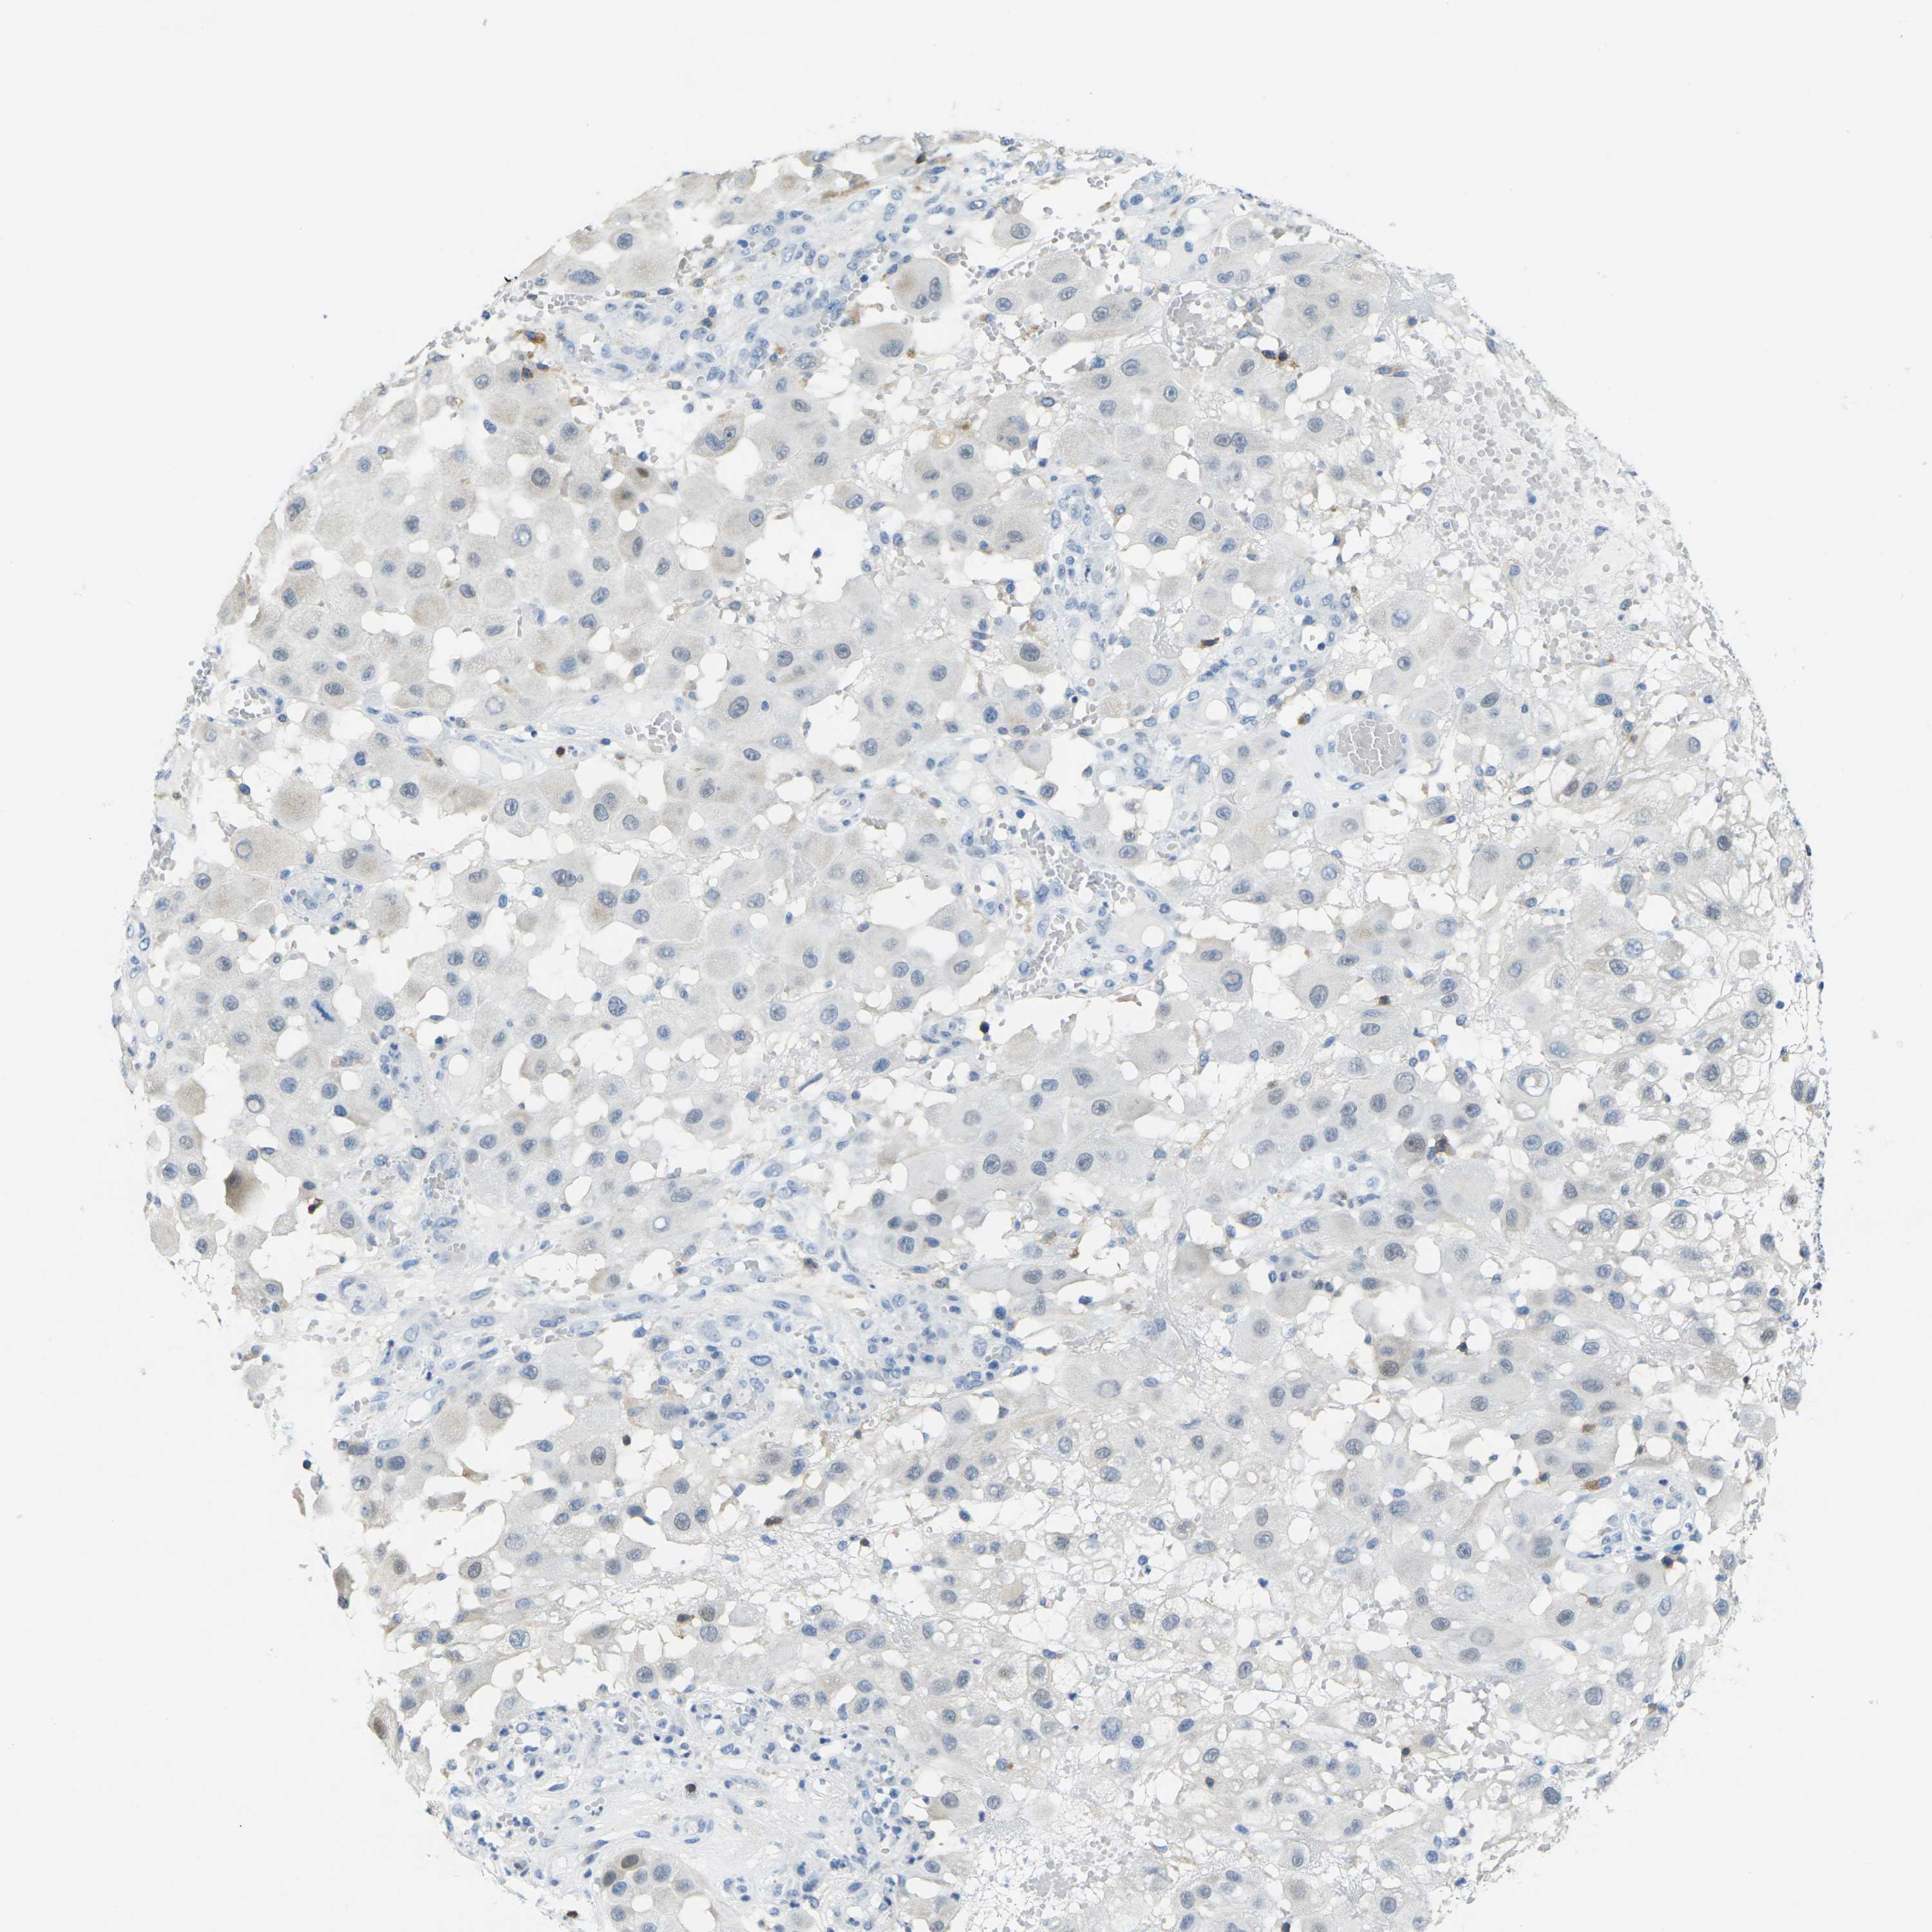

MELANOMA - Protein expressioni

A mouse-over function shows sample information and annotation data. Click on an image to view it in a full screen mode. Samples can be filtered based on level of antibody staining by selecting one or several of the following categories: high, medium, low and not detected. The assay and annotation is described here.

Note that samples used for immunohistochemistry by the Human Protein Atlas do not correspond to samples in the TCGA dataset.

Antibody stainingi

Antibody staining in the annotated cell types in the current human tissue is reported as not detected, low, medium, or high, based on conventional immunohistochemistry profiling in selected tissues. This score is based on the combination of the staining intensity and fraction of stained cells.

Each image is clickable and will lead to virtual microscopy that enables deeper exploration of all samples and also displays staining intensity scores, fraction scores and subcellular localization as well as patient and tissue information for each sample.

Antibody HPA071778

Antibody CAB013055

Malignant melanoma, NOS

Malignant melanoma, Metastatic site

Malignant melanoma in situ